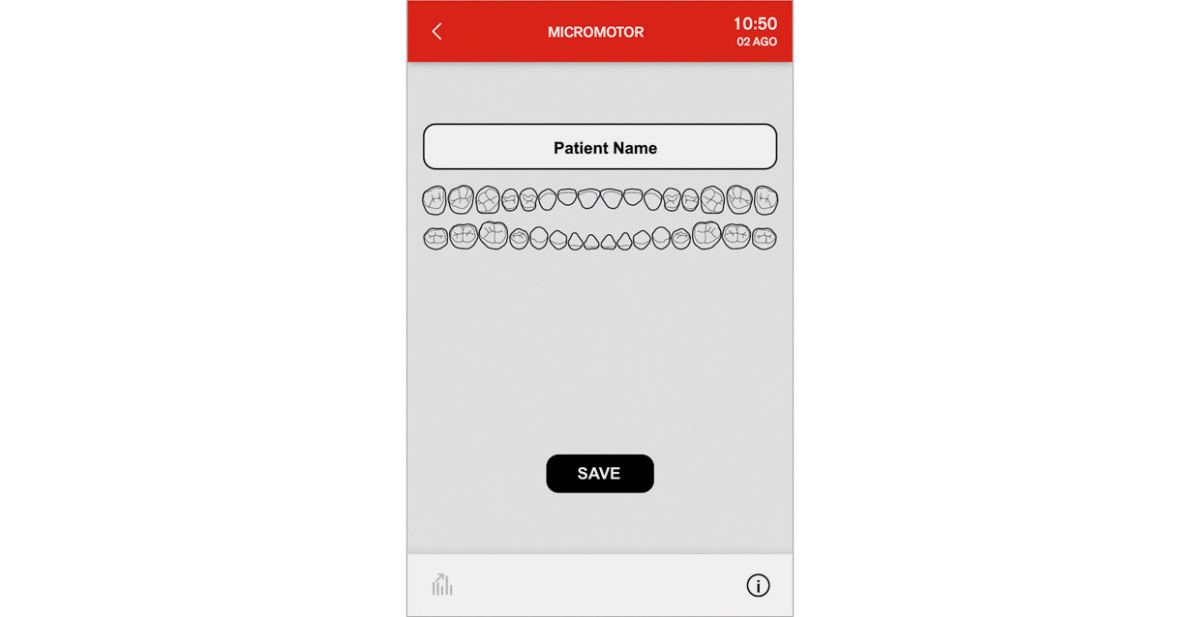

Classe A7 предоставляет комплексную систему эндодонтии, которая оптимизирует эргономику лечения корневых каналов. Эта система включает микромотор, набор подходящих угловых наконечников и файлов для эндодонтии, функции Autostop, Autoreverse, Autoforward и электронный апекс локатор. Всеми функциями можно точно управлять с панели Full Touch. Во время лечения отображаются необходимые данные, обеспечивая полный контроль. ПО автоматически задает крутящий момент и скорость; также стоматологи могут устанавливать значения согласно личным требованиям.

Расстояние до апекса выводится на дисплей при инструментальной обработке корневого канала. Приближение апекса проверяется программой ENDO. При достижении апекса функция Apex-Stop останавливает вращение микромотора.